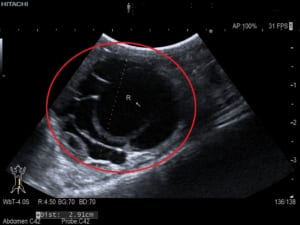

エキゾチック獣医は、身体検査を行っているときに、腹部の不快感とともにモルモットの内部に大きな嚢胞または一対の嚢胞を感じることがあります。獣医師は、嚢胞性卵巣の有無を確認するために X 線または腹部超音波検査を推奨する場合があります。診断を行うために、腹部と嚢胞に針を挿入して嚢胞内の液体を採取しようとすることもあります。